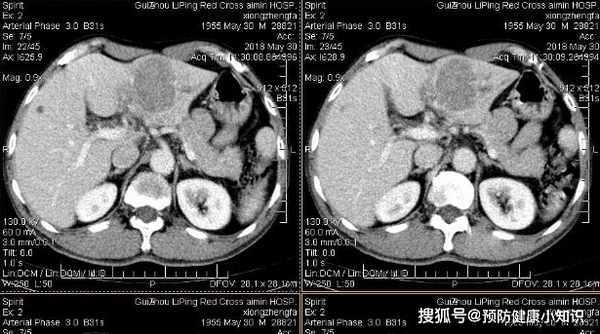

劉大哥躺在病床上,看著檢查報告的兩個大字"肝癌",臉色煞白。

醫生告訴他,你的甲胎蛋白指數高達480ug/L,肝部有明顯占位,而且以前就肝病徵兆,你常吃隔夜飯菜的習慣對肝臟損傷很大,而這是導致肝癌產生的主要原因。